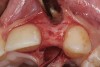

Fig 1 and Fig 2. Pretreatment photographs. Patient at 9 years of age on presentation.

A 9-year-old girl, referred to a prosthodontic office by her pediatric dentist, presented with her mother’s chief complaint: “The kids are teasing her about her big front tooth.” Findings from radiographic and clinical examinations revealed fused maxillary central-peg lateral incisors, teeth Nos. 7 and 8, and a congenitally missing lateral incisor, tooth No. 10 (Figure 1 through Figure 3). An implant was selected as the ideal treatment to replace tooth No. 10 when somatic growth was complete. A diagnostic wax-up was fabricated to determine if the fused tooth could be made to resemble two teeth, using pink composite to give the illusion of an interproximal papilla. The patient was referred for an orthodontic consultation to plan for closure of the diastema between teeth Nos. 8 and 9 and achievement of proper alignment for implant No. 10. The patient was also referred to a periodontist for pretreatment assessment of the tooth No. 10 site. An endodontist was consulted should exposure of the large pulp occur during tooth preparation.